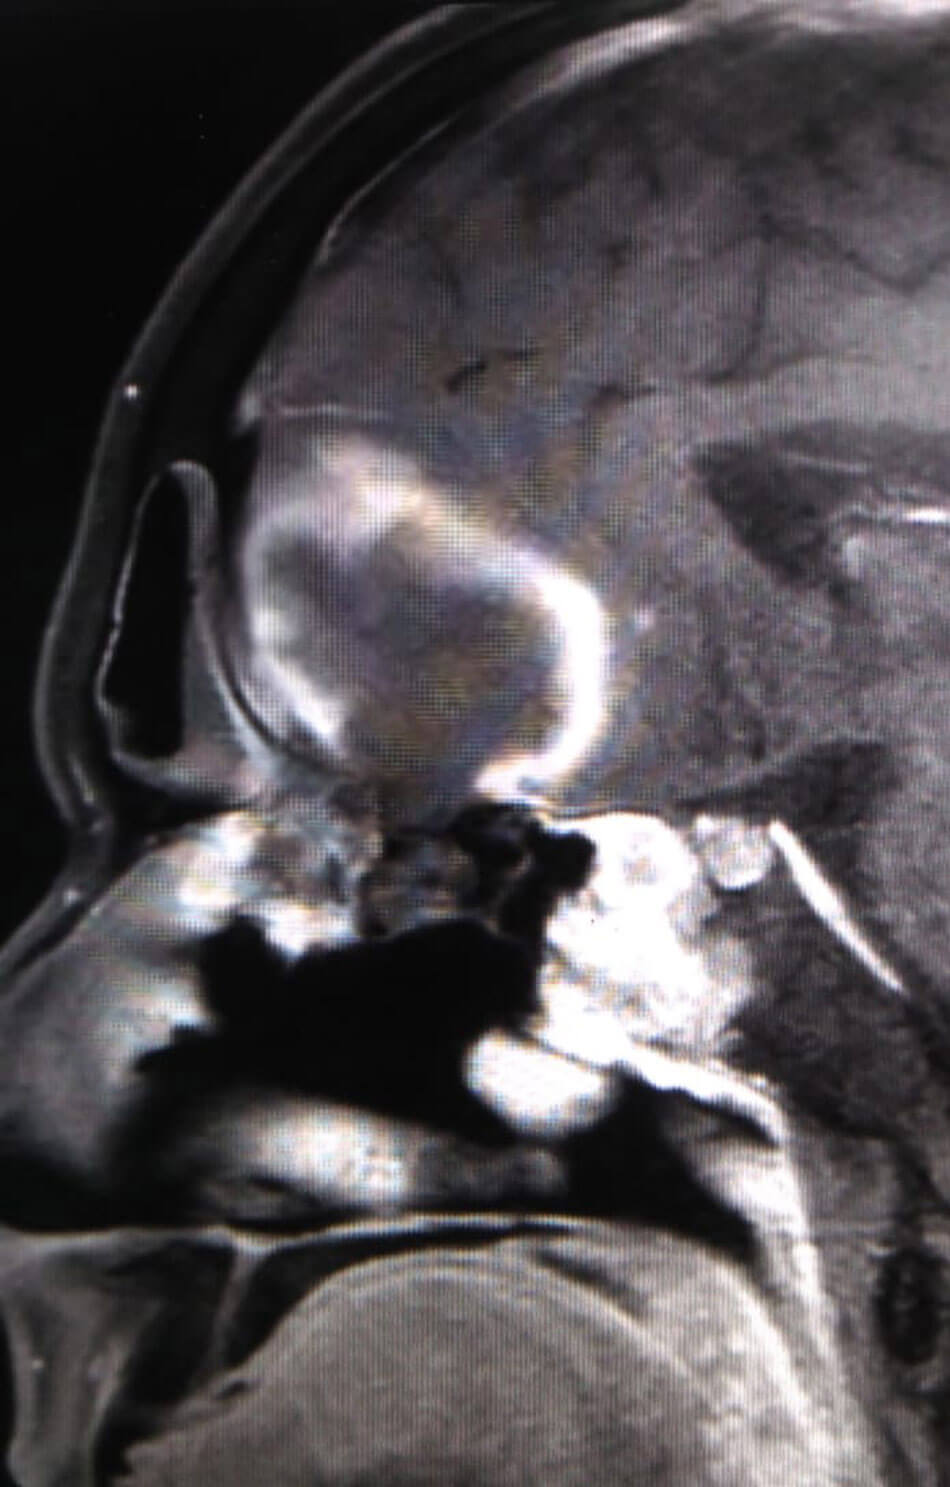

MRI scans of a patient with ROCM showing a large frontal lobe brain abscess

with necrosis of the cribriform plate (coronal and sagittal views).